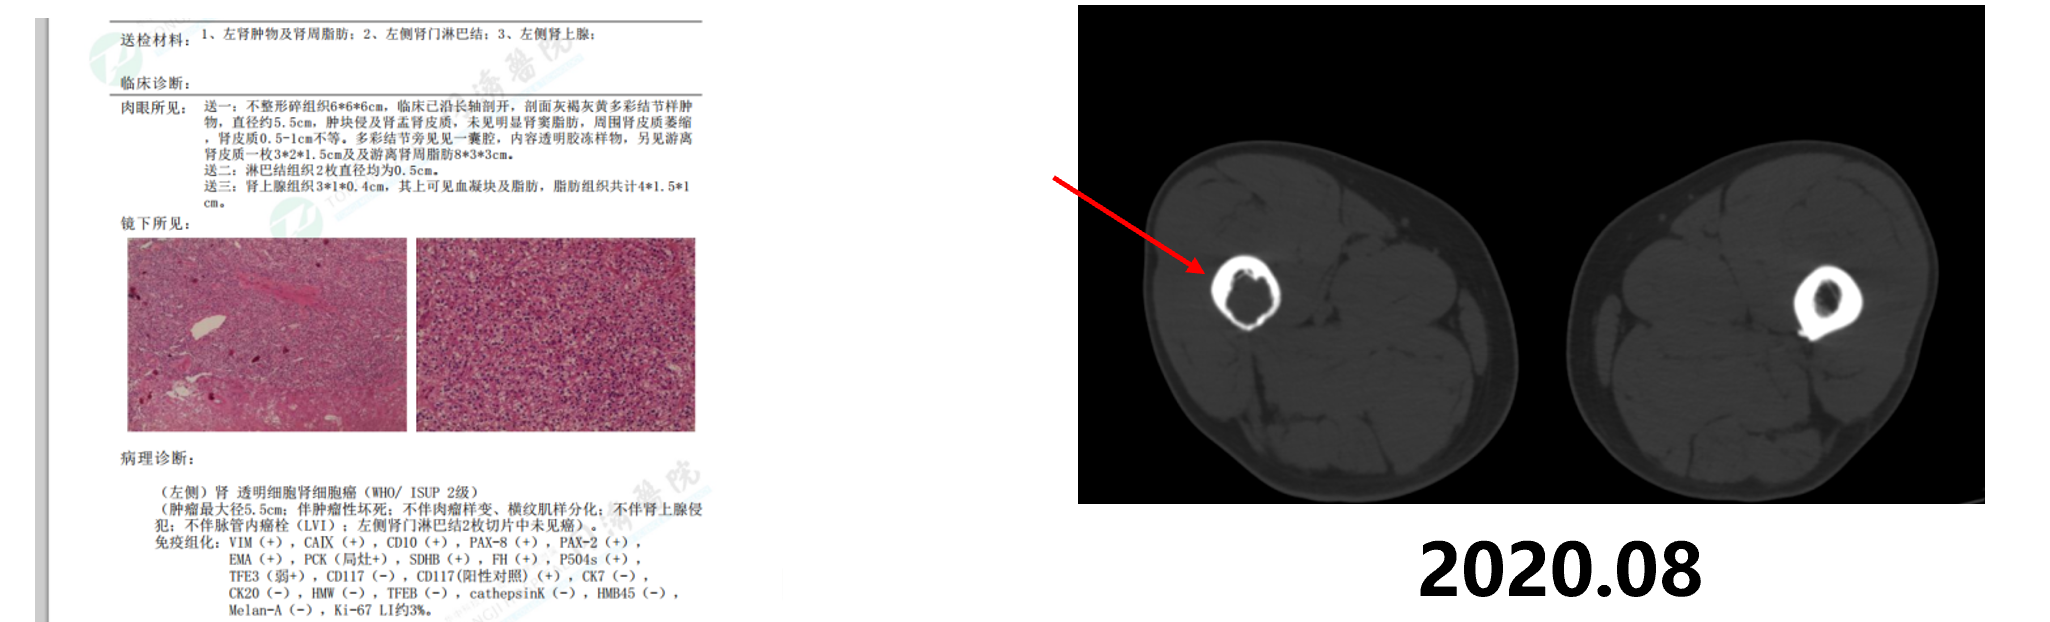

2020.7月PET-CT示:1、左肾上极软组织密度肿块,代谢增高,考虑左肾癌,2、左侧肾门区多发淋巴结,代谢不高,考虑淋巴结转移,3、右侧股骨上段局部骨质破坏,代谢增高,考虑骨转移。

2020年8月因左肾肿瘤在我院行左肾部分切除术,术后病检提示:(左侧)肾透明细胞肾细胞癌(WHO/ ISUP 2级。术后服用培唑帕尼,患者出现肝功能异常,更换阿昔替尼靶向治疗。